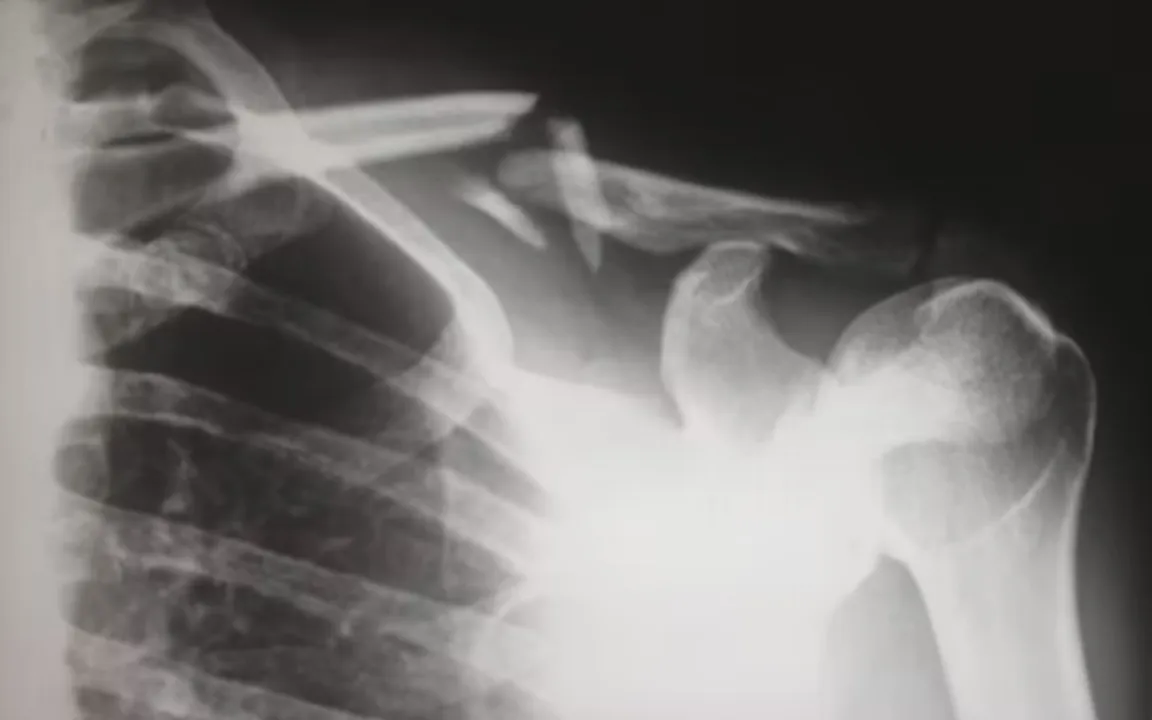

Перелом.

Перелом.© unsplash.com

Результаты эксперимента, опубликованные в журнале CRANIO: The Journal of Craniomandibular and Sleep Practice, показали, что участники с обструктивным апноэ сна имели значительно более низкую минеральную плотность костей, чем участники без этого состояния. Полученные данные не изменились после поправки на возраст, пол и вес участников.